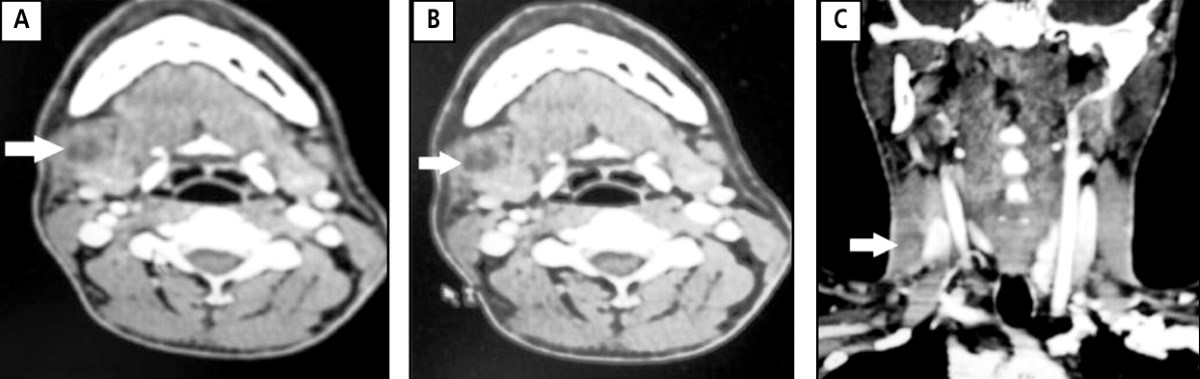

Горизонтальная (А и В) и корональная (С) компьютерная томография у 24-летнего мужчины: гнойный лимфаденит подчелюстных узлов (ниже угла правой нижней челюсти).